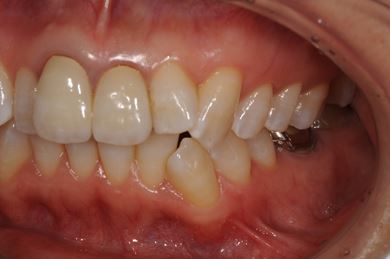

インプラント治療+セラミック治療

| 性別/年齢 | 女性 / 42歳 | ||||||||||||||||||||||||||||||||

| 主訴 | 別の病院で、右奥歯の根の部分にインプラント治療が必要と言われたので、セカンドオピニオンを希望。 | ||||||||||||||||||||||||||||||||

| 治療方針 | 右下奥、保存不能の歯を抜歯し、インプラント治療にて、機能的・審美的回復を行う。 | ||||||||||||||||||||||||||||||||

| 治療内容 | インプラント1本、メタルボンドセラミッククラウン2本(メタルボンド用土台1本) | ||||||||||||||||||||||||||||||||

| 総治療費 | 502,740円 | ||||||||||||||||||||||||||||||||

| 治療期間 | 1年3ヶ月 |